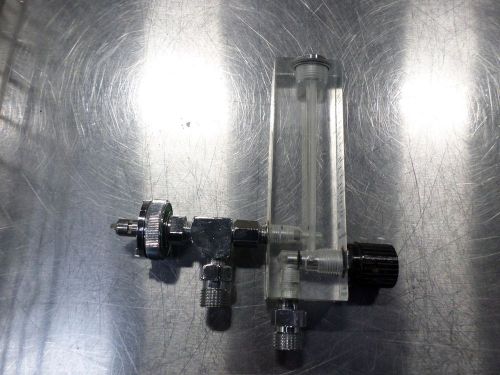

Allied Timeter Oxygen Flow Meter

Timeter Instrument Oxygen Flow Meter